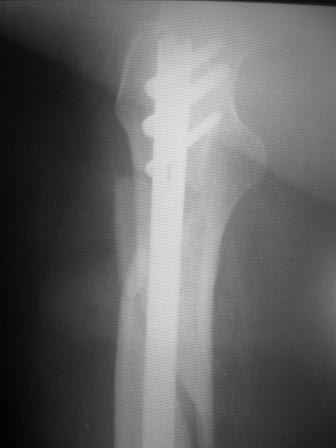

На мой взгляд если у пациентки "куча" сопутствующей патологии, то консервативно вы получите такую же "кучу" осложнений-пролежни, декомпенсация всего. Оперировать-проксимальным бедренным штифтом длинной версией. И ранняя активизация пациентки. Есть опыт и наблюдения таких пациентов, старались оперировать всех.

Уважаемый Максим, поддерживаю Вашу тактику на сто процентов. Более того скажу, что было в моей практике: установка блокированного бедренного стержня под местной анестезией (инфильтрационной), больная инвалид первой группы-анестезиологи отказались от больной. Выписана из отделения через 10-ть суток с объёмом движений до перелома (обслужи себя сам). Автору поста, чем меньше продержите до операции, тем лучше эфект от лечения (но без фанатизма).

Если правильно вести правильный PFN, нагрузку можно не ограничивать.